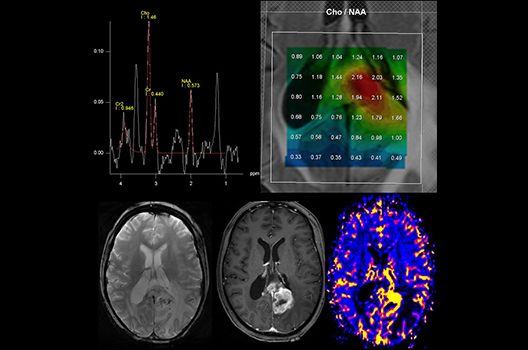

Die Schwerpunkte in der MR-Forschung liegen in der multiparametrischen und funktionellen Bildgebung bei onkologischen und anderen, neuroradiologischen Fragestellungen und umfassen die Anwendung modernster MR-Verfahren sowie die Untersuchung an Hochfeld-Geräten.

Die Magnetresonanztomographie (MRT) ist ein Verfahren, bei dem durch magnetische Kräfte Bilder des Körperinneren angefertigt werden. In der Neuroradiologie können manchmal kleinste Veränderungen schwere Folgen haben; daher forschen wir an der Entwicklung hochauflösender MRT-Sequenzen, mit denen diese Prozesse und auch einzelne Nervenfaserbahnen sichtbar gemacht werden können. Darüber hinaus sind bei vielen Erkrankungen des Gehirns die Blutgefäße betroffen. Daher arbeiten wir an der Neu- und Weiterentwicklung von MRT-Sequenzen zur Darstellung der Blutgefäße und zur Blutflussanalyse (sog. „Angio-MRT“). Einen besonderen Forschungsschwerpunkt unserer Klinik stellen die MR-Protonenspektroskopie und die funktionelle MRT dar, mit denen die Analyse einzelner chemischer Substanzen im Hirngewebe oder die Darstellung ausgewählter Hirnfunktionen möglich ist.

Die Hybridbildgebung mittels PET/MRT spielt insbesondere in der onkologischen Bildgebung eine wichtige Rolle. Eine mögliche Fragestellung ist die Unterscheidung zwischen einem Tumorrezidiv oder therapeutisch assoziierten Veränderungen insbesondere dann, wenn diese Frage mittels MRT alleine nicht beantwortet werden kann.

Die bildgebende Diagnostik und Verlaufsbeurteilung von Tumoren des Nervensystems ist einer der klinischen und Forschungsschwerpunkte unserer Abteilung. Eine besondere Bedeutung kommt der Hybrid-Bildgebung zu. Das Universitätsklinikum verfügt über einen integrierten Ganzkörper-PET/MRT-Scanner, der die Vorteile der MRT-Bildgebung und der Positronenemissionstherapie (PET) vereinigt. Aufgrund der langjährigen klinischen Arbeit und Forschungstätigkeit mit diesem Gerät hat die Neuroradiologie Tübingen maßgeblich zur Etablierung dieses Verfahrens beigetragen. Auch weiterhin forschen wir intensiv an neuen Methoden zur frühen Einordnung von Tumoren und insbesondere Tumorrezidiven, die mit anderen Methoden häufig nicht erfasst werden können.